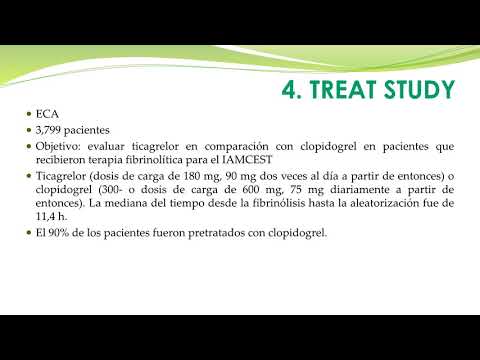

Tratamiento con Ticagrelor en pacientes con IAM. Dra. Florencia Anzivino. Residencia de Cardiología. Hospital C. Argerich. Buenos Aires

Estrategias fármaco invasiva para ATC primaria. Dr. Juan Pablo Lestard. Residencia de Cardiología. Hospital C. Argerich. Buenos Aires